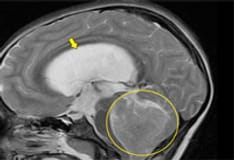

The brainstem auditory evoked potential (BAEP), or brainstem auditory evoked response (BAER), measures the functioning of the auditory nerve and auditory pathways in the brainstem (see the image below).